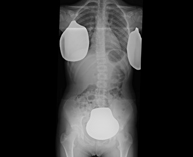

- Abdomen X-ray

An abdominal X-ray uses a small dose of radiation to obtain a two-dimensional image of the abdomen with its anatomical structures (stomach, small intestine, large intestine, liver, pancreas, kidneys, bladder, bony pelvis, etc.).

- UIV (Pielografia descendent)

La urografia intravenosa (UIV) consisteix en l'obtenció d'imatges radiològiques seriades del ronyó, vies urinàries i bufeta. Aquest estudi requereix sempre l'ús d'un contrast iodat. - Cistografía (CUMS)